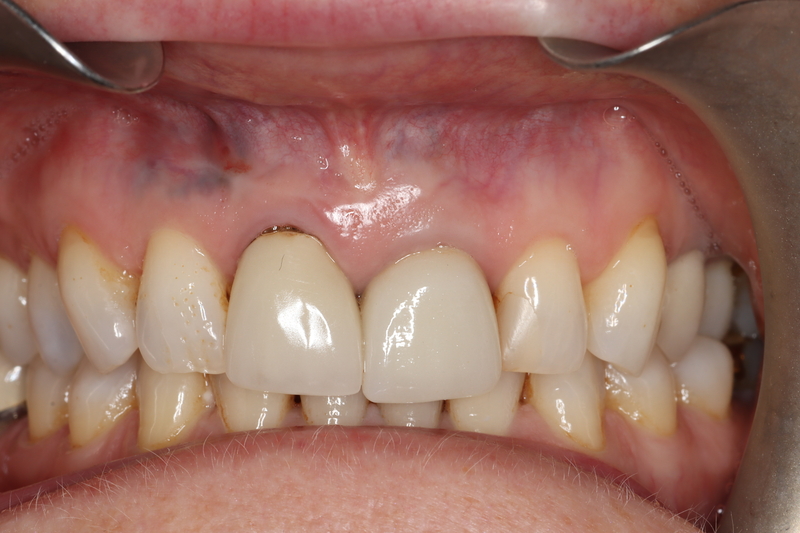

Case 26 – Endodontics

Repeat apicectomy with grafting